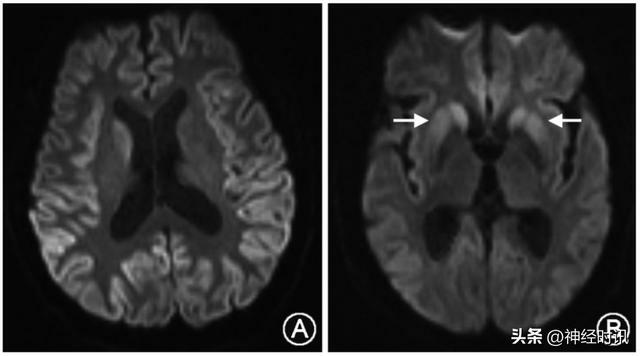

頭顱MRI是診斷克-雅病的重要手段之一,絕大多數CJD患者可觀察到特徵性改變,即彌散加權成像(DWI)或液體衰減反轉恢復序列(FLAIR)上出現至少兩個皮質區域(額、顳、頂、枕;圖2A)和(或)基底節區[尾狀核和(或)殼核]高信號(圖2B)。

A:雙側額、顳、頂、枕葉皮 質及右側尾狀核頭彌散加權成像(DWI)高信號;B:雙側額、顳、 枕葉及尾狀核頭和殼核 DWI 高信號(箭頭)